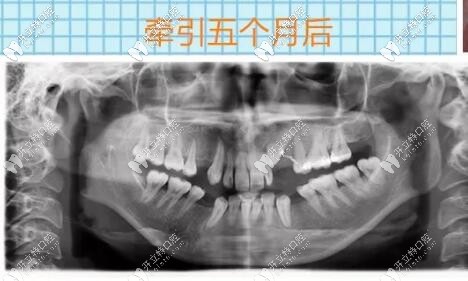

埋伏牙開窗牽引5個月后

導(dǎo)萌手術(shù)結(jié)束之后的幾個月以后,逐漸迎來了曙光,看到了埋伏牙逐漸牽引出來,那種激動的心情無法言語,時間過去太快了,到目前為止仍不后悔當(dāng)初的決定。